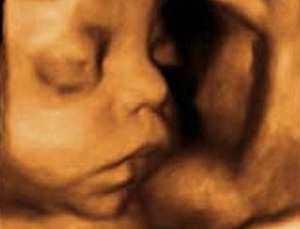

Con 25 semanas de embarazo tu bebé pesa ya 700 gramos y mide 22 centímetros desde la cabeza al final de la columna en la semana 25 de embarazo. La razón es que el bebé todavía es pequeño y tiene espacio suficiente para moverse y cambiar de posición varias veces durante el día. Los párpados del niño se abren y se pueden ver los ojos. La lengua sale de la boca y se mueve hacia los lados. Tu hijo bosteza, sonríe y empieza a hacer gestos como si de un niño mayor se tratase.

ya pesa 1.250 gramos y mide unos 37 centímetros de la cabeza a los pies con 29 semanas de embarazo. Se produce un notable desarrollo de la cara del bebé: Ya tiene cejas, pestañas y abre y cierra los ojos. Todavía el diámetro de su cabeza es mayor que el de su abdomen. Esta situación se suele invertir hacia la semana 35 de embarazo, momento en que la medida del abdomen del bebé supera el diámetro de la cabeza.